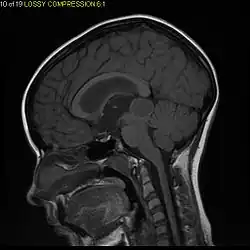

Pilocytic astrocytoma (and its variant pilomyxoid astrocytoma) is a brain tumor that occurs most commonly in children and young adults (in the first 20 years of life). They usually arise in the cerebellum, near the brainstem, in the hypothalamic region, or the optic chiasm, but they may occur in any area where astrocytes are present, including the cerebral hemispheres and the spinal cord. These tumors are usually slow growing and benign, corresponding to WHO malignancy grade 1.[1]

Usually – depending on the interview of the patient and after a clinical exam which includes a neurological exam and an ophthalmological exam – a CT scan and/or an MRI scan will be performed to confirm the presence of a tumor. They are usually easily distinguishable from normal brain structures using these imaging techniques. A special dye may be injected into a vein before these scans to provide contrast and make tumors easier to identify. Pilocytic astrocytomas are typically clearly visible on such scans, but it is often difficult to say based on imaging alone what type of tumor is present.

Pilocytic astrocytomas are often cystic tumors, and, if solid, tend to be well-circumscribed.